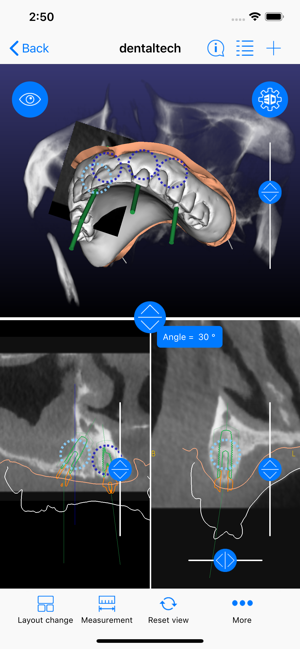

ICX-Magellan X is a cloud-based Software concept used for CBCT-Analysis and to create Implant-Treatment plans.

The ICX-Magellan X App completes this System primarily regarding communication, treatment-plans that were prepared at the pc can be shared with other users in real-time, commented, changed or confirmed.

The App can be integrated supporting any workflow; existing treatment-plans can be recalled, edited or used for patient-education anywhere anytime.